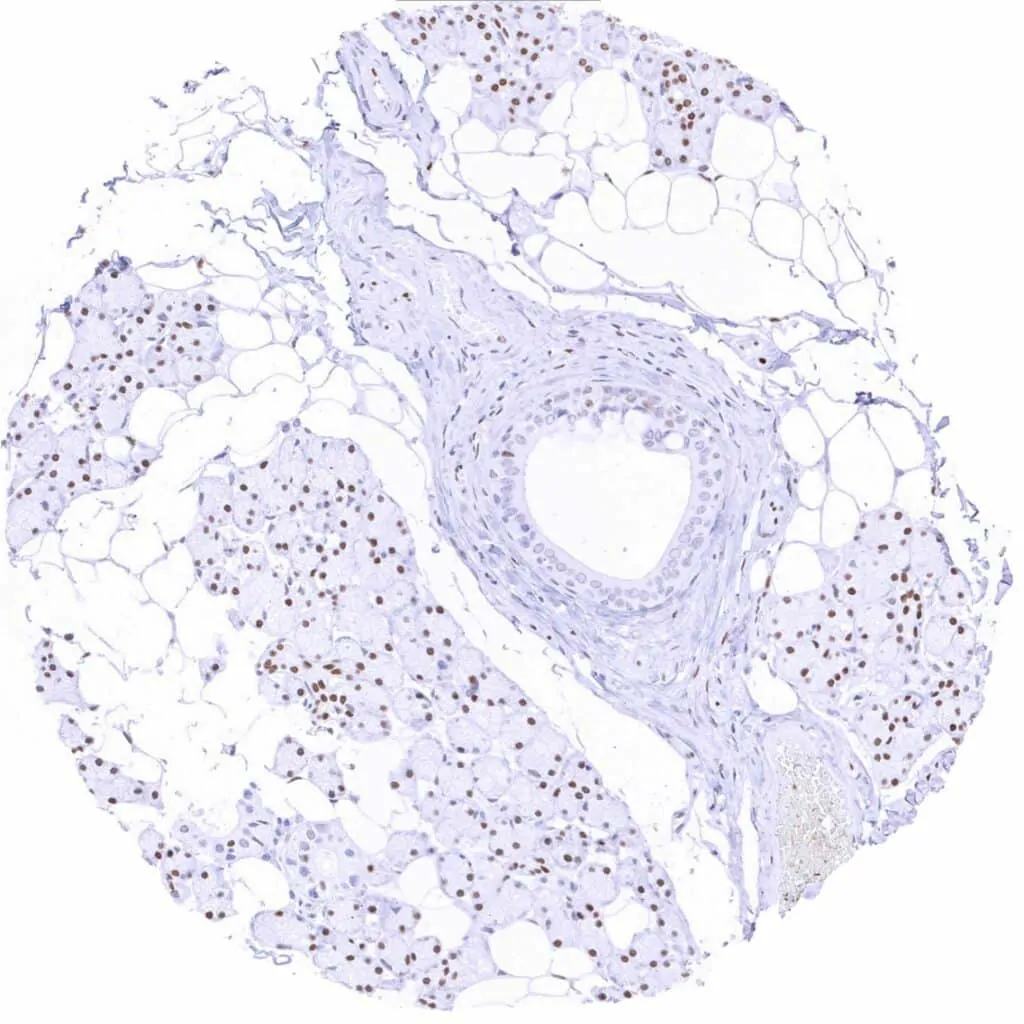

Fat